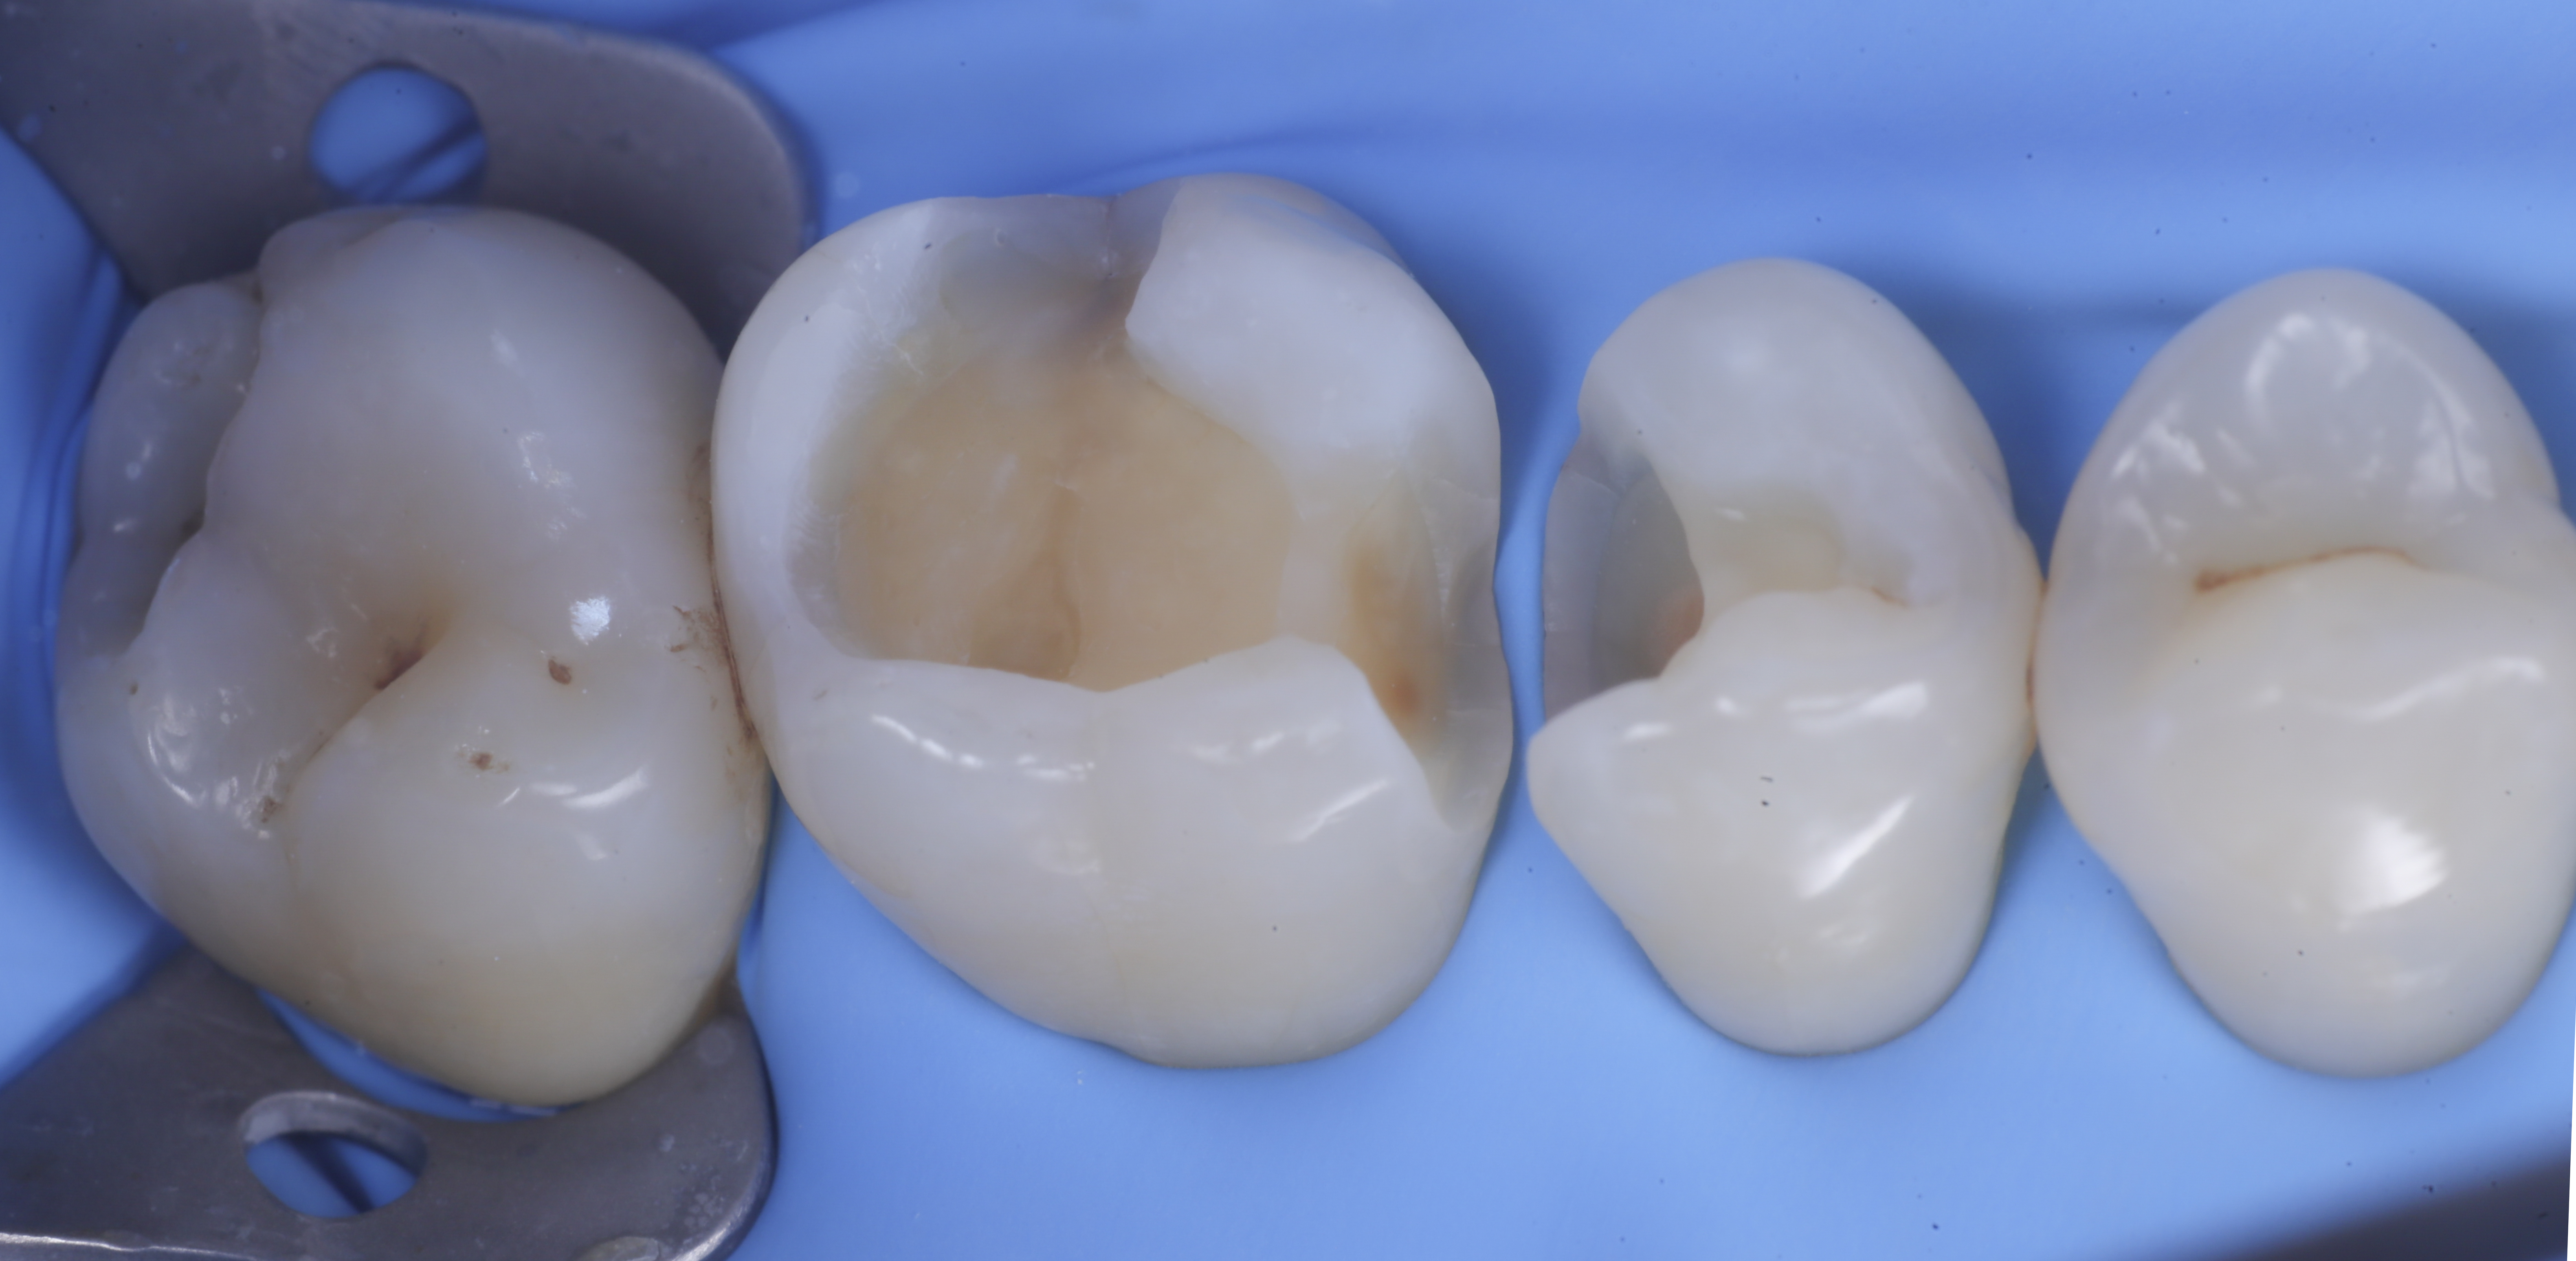

foto 6 Aspetto occlusale delle pareti interprossimali appena create

foto 7 Aspetto vestibolare delle pareti interprossimali appena create

foto 8 Modellazione ed aspetto occlusale